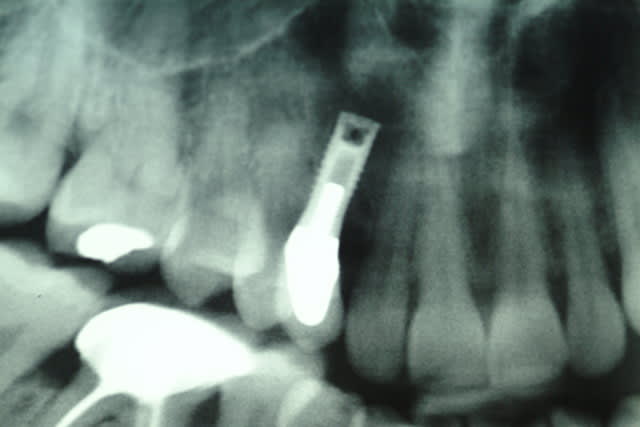

Implant sur la 13 posé il y'à 15 ans.

La 13 était dans le palais, extraite qqs mois avant l'implantation.

j'ai juste une pano, mais rien de spécial dessus, implant cylindrique, à vue d'oeil, diam 4, long 10 à 12 mm.

Voici les clichés de l'implant sur 13

marcB6